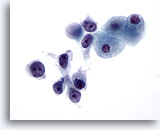

画像 3

肝FNA – 良性肝細胞

核はわずかに大小不同であり、反応性変化を来した肝細胞に典型的な低N/C比を示します。微小な細胞質空胞および細胞質内色素がみられます。

60倍

画像 3

肝FNA – 良性肝細胞

核はわずかに大小不同であり、反応性変化を来した肝細胞に典型的な低N/C比を示します。微小な細胞質空胞および細胞質内色素がみられます。

60倍